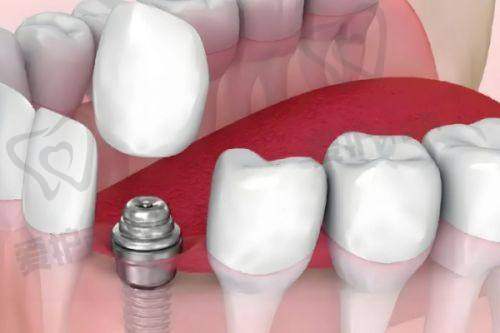

柳书喻医生擅长多种种植牙技术,如3D数字化种植技术、微创种植技术、水镭射种植技术以及即拔即种技术等。这些技术各有优势,能够满足不同患者的需求。

3D数字化种植技术是一种较为精良的种植技术。它通过计算机辅助设计和制造,能够严谨地模拟种植过程,确定种植体的位置、角度和深度。这样可以提高种植的正确性和成功几率,减少手术风险。柳书喻医生熟练掌握这项技术,能够为患者提供更加精细的种植治疗。

微创种植技术是柳书喻医生的拿手好戏之一。传统的种植牙手术创口较大,患者术后修复时间较长。而柳书喻医生的微创种植技术创口仅5mm,大大减少了对患者口腔组织的损伤。患者在术后疼痛较轻,修复速度也更快。